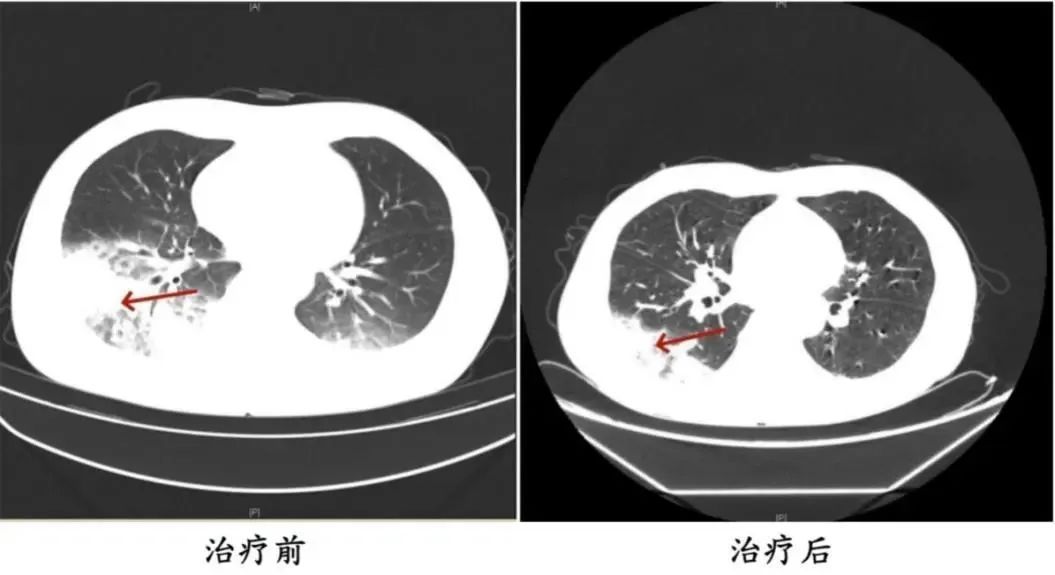

周先生治疗前后的肺部CT影像

家人见状,立即将他送医。胸部CT显示李先生的左肺已出现大面积白色影像,几乎占据一半肺部。经过检测,最终确认是嗜肺军团菌肺炎。

医生询问发现,周先生此前驾车出差,因为天气热,他启动了久未清洗的车载空调,每天在车上的时间超过十个小时,回来后就出现了如上症状。经过检查,最终确诊为军团菌肺炎。